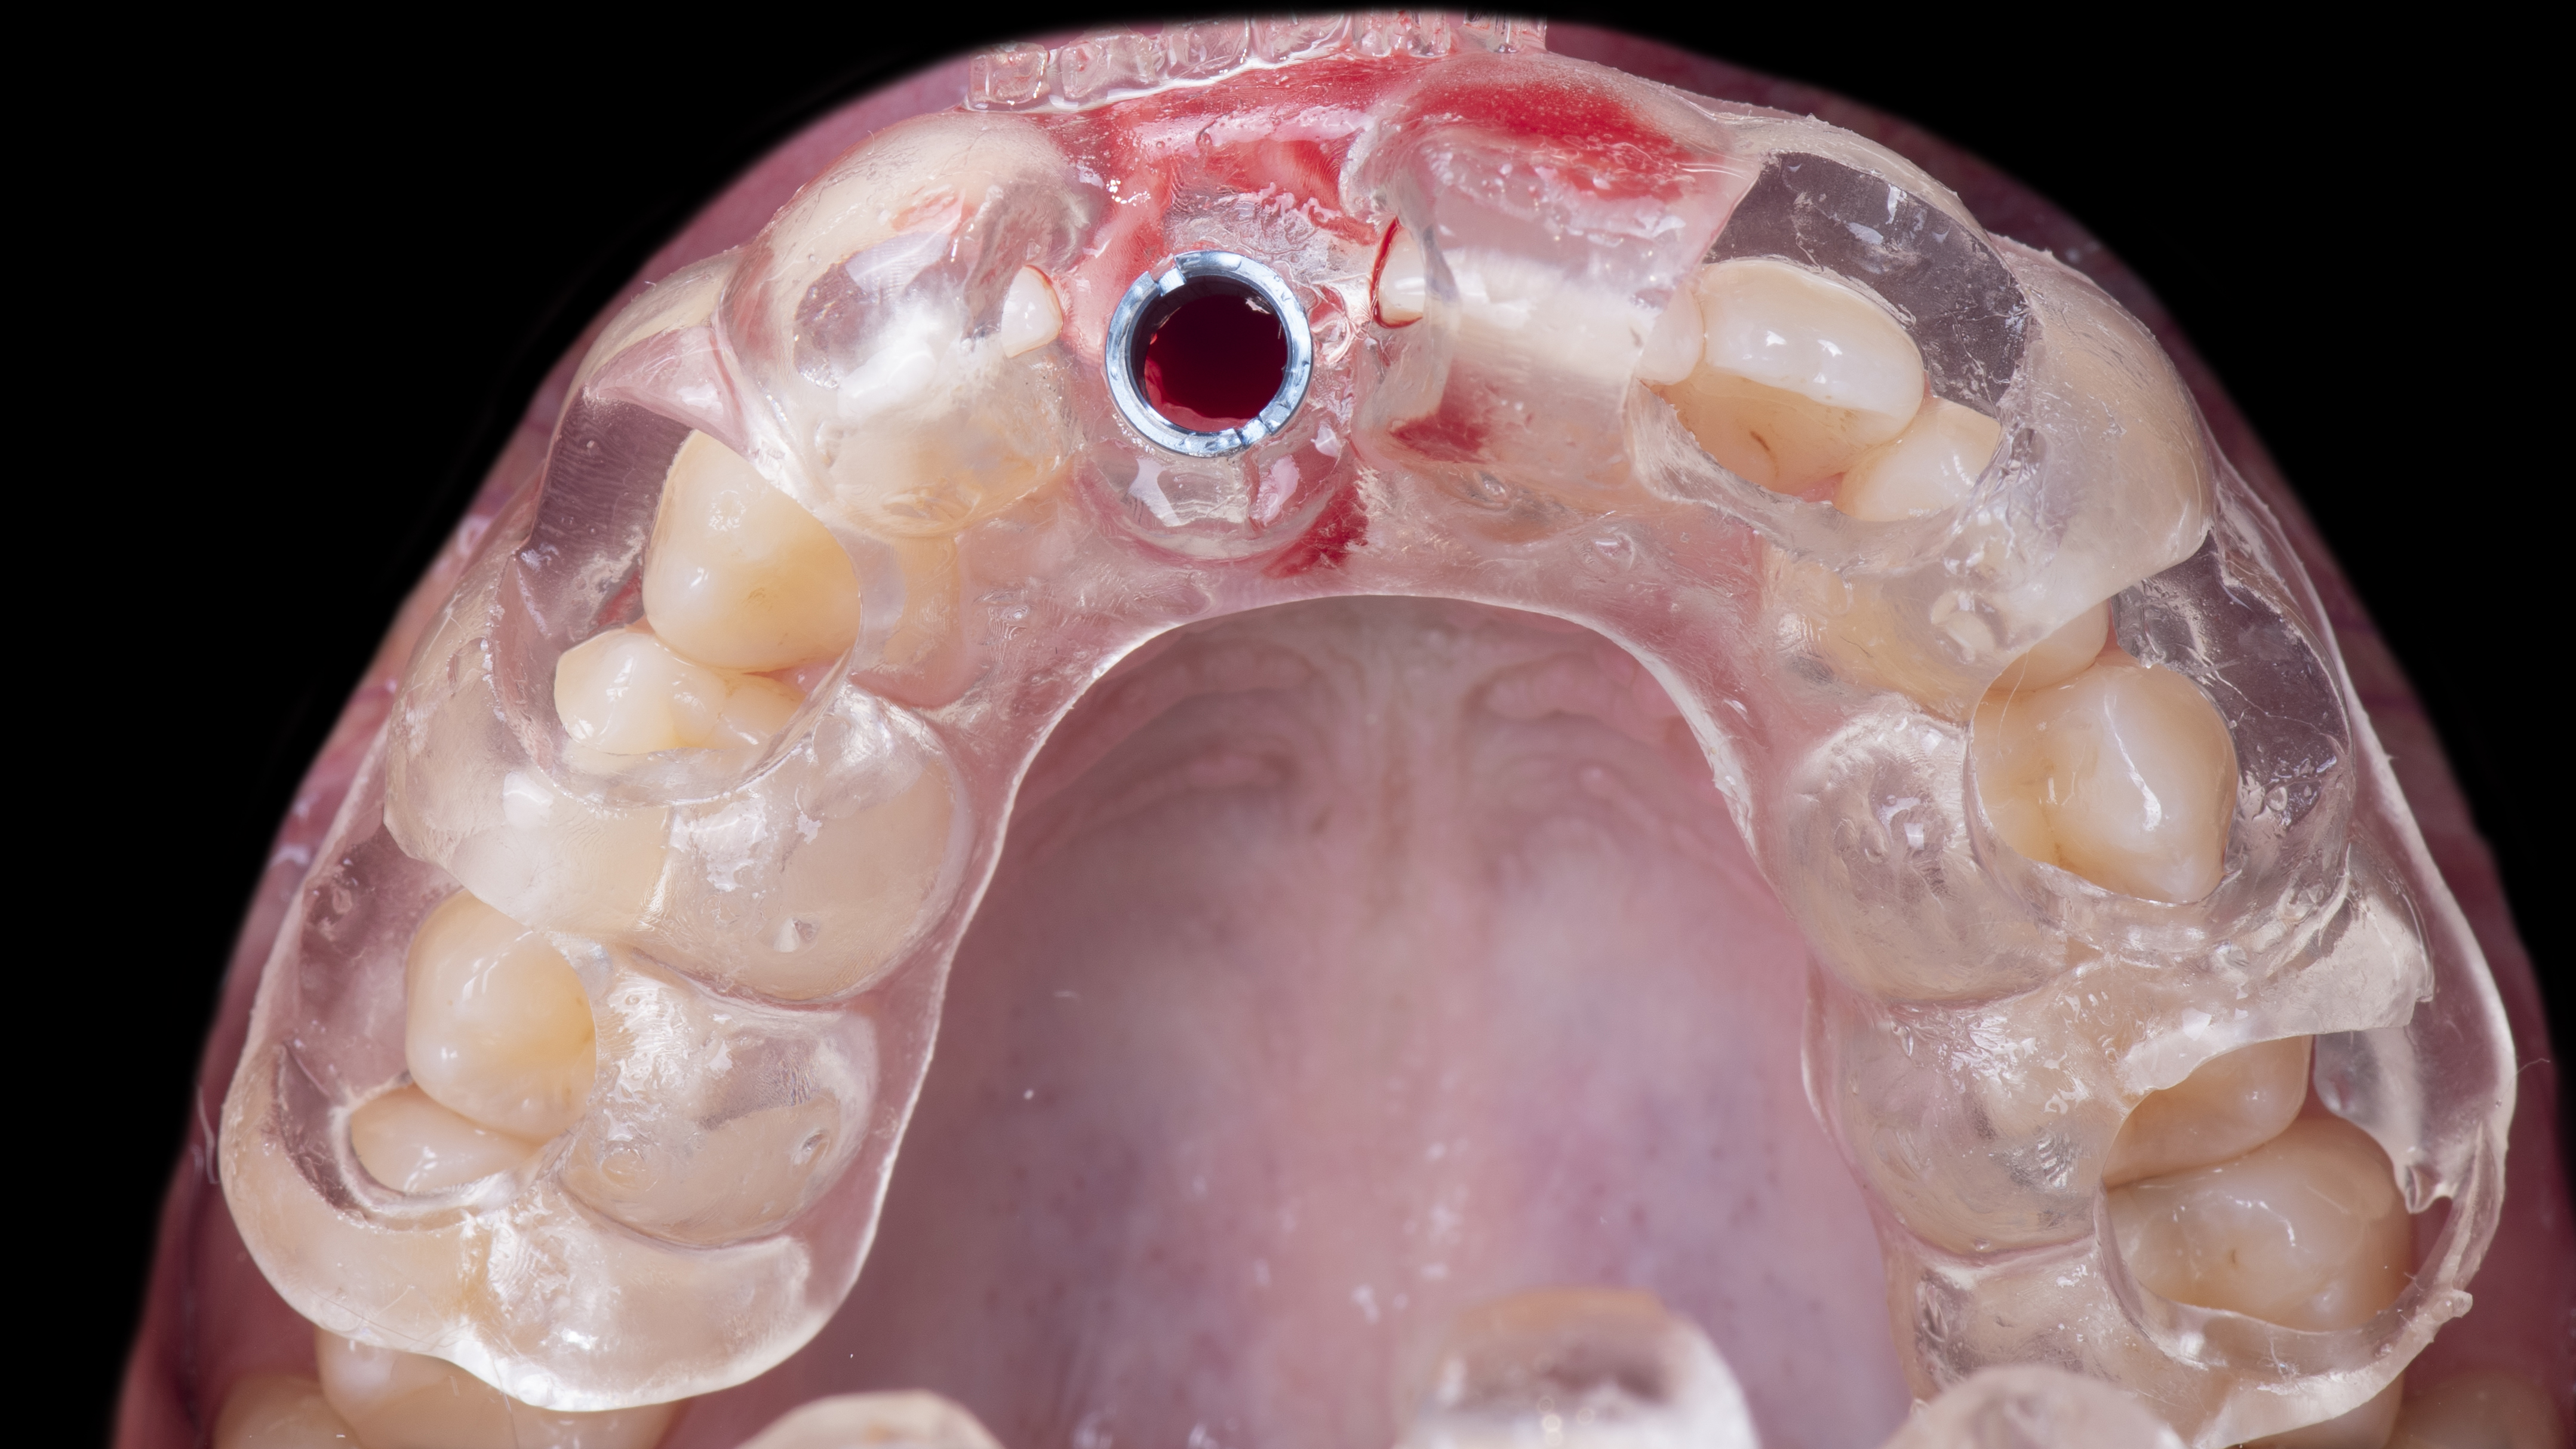

Mise en place du guide chirurgical imprimé au cabinet. Réalisation des forages et mise en place de l’implant au travers du guide chirurgical (Photo 11).